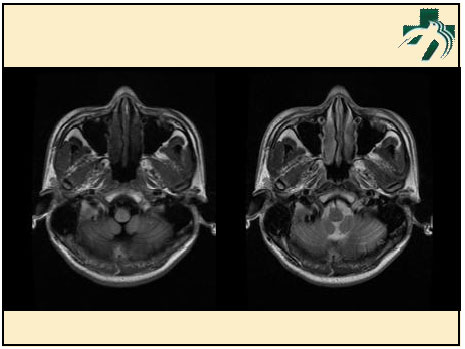

奴卡氏菌感染

第九期三博

读片会

病例之四

北京协和医院 提供

男性,22岁。自觉虫咬后皮疹、肢体麻木4月